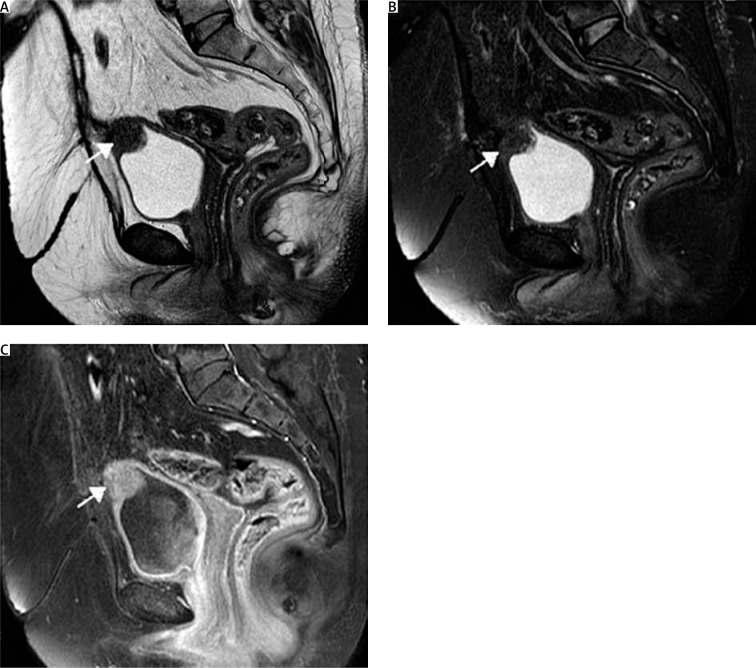

膀胱内的病变给诊断带来了复杂性,因此需要采取个性化的治疗方法。宫颈内膜异位症是一种源自穆勒氏组织的罕见疾病,其特点是宫颈内膜腺体良性浸润,主要影响膀胱。尽管没有明确的症状,但必须进行细致的术前评估,以确保准确诊断和最佳的手术干预。虽然宫颈内膜异位症通常是良性的,但最近的病例暗示它可能与腺癌有关,这就强调了精细治疗的必要性。宫颈内膜异位症的治疗缺乏共识,建议的手术方式包括经尿道切除术或部分膀胱切除术。在本病例中,一名 47 岁的女性因子宫腺肌症切除子宫后出现慢性盆腔疼痛而到我科就诊。影像学检查发现,膀胱穹隆处有一个实性病灶。因此,为了保护膀胱的完整性,我们对其进行了分段膀胱切除术,只对肿瘤进行环形切除,并尽量减少手术游离缘。组织病理分析证实了宫颈内膜异位症的诊断。尽管膀胱宫颈内膜异位症的病例报道仍然有限,但这一病例为我们了解和处理这一疾病提供了宝贵的启示。它强调了准确诊断和有针对性的手术干预在优化患者预后和减少术后并发症方面的关键作用,其中单纯肿瘤切除术是一种前景广阔的可行方法。

The diagnostic complexities posed by lesions within the urinary bladder underscore the need for personalised management approaches. Endocervicosis, a rare condition stemming from Müllerian tissue, is characterised by the benign infiltration of endocervical glands, predominantly affecting the urinary bladder. Despite the absence of definitive symptoms, meticulous preoperative assessment is imperative to ensure precise diagnosis and optimal surgical intervention. While typically benign, recent cases have hinted at a potential association with adenocarcinoma, underscoring the necessity for meticulous management. The management of endocervicosis lacks consensus, with suggested surgical modalities including transurethral resection or partial cystectomy. In this case, a 47-year-old woman presented to our department with chronic pelvic pain following hysterectomy for adenomyosis. Imaging tests revealed a solid lesion situated at the dome of the urinary bladder. Consequently, a segmental cystectomy with circular tumour-only excision, with minimal free surgical margins, was undertaken to preserve bladder integrity. Histopathological analysis confirmed the diagnosis of endocervicosis. While the reported cases of urinary bladder endocervicosis remain limited, this instance contributes valuable insights into its understanding and management. It underscores the pivotal role of accurate diagnosis and tailored surgical intervention in optimising patient outcomes and mitigating postoperative complications, with tumour-only excision emerging as a promising and feasible approach.